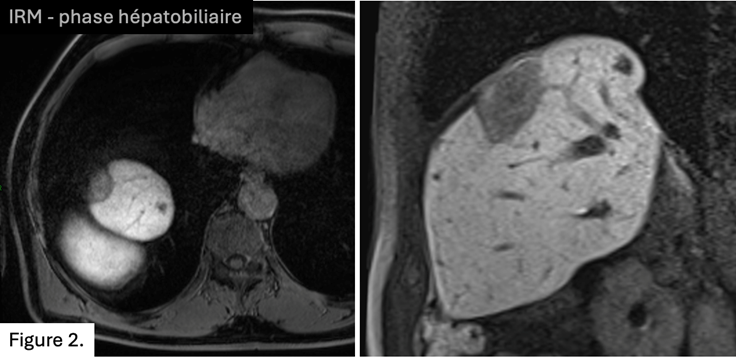

Au cours du suivi, apparition d’une hernie diaphragmatique et d’une lésion centimétrique au dôme du segment 𝗩𝗜𝗜 (𝗙𝗶𝗴𝘂𝗿𝗲 𝟮)